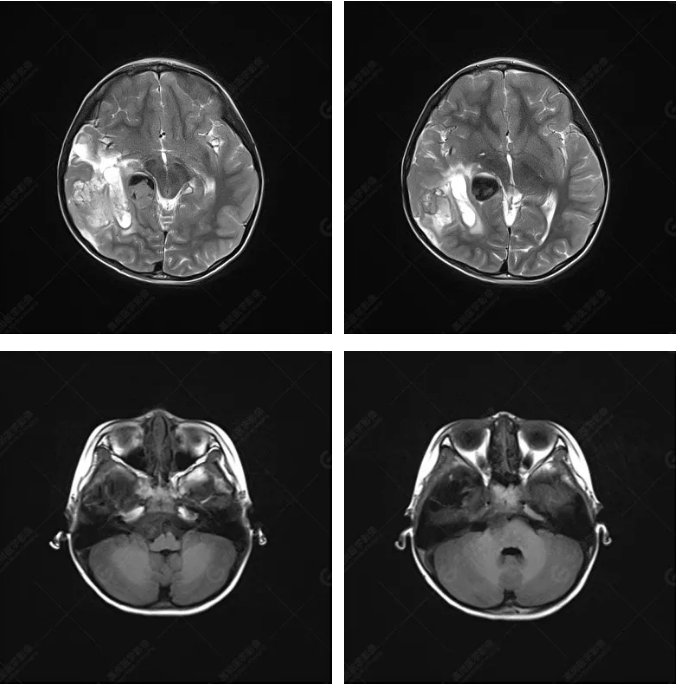

右側(cè)顳葉腫瘤切除術(shù)后(具體不詳):右側(cè)顳部骨質(zhì)不連續(xù)呈術(shù)后改變,右側(cè)顳葉術(shù)區(qū)見(jiàn)片狀長(zhǎng)T1長(zhǎng)T2信號(hào)影,F(xiàn)LAIR呈低信號(hào);術(shù)區(qū)后方右側(cè)顳枕葉見(jiàn)一巨大占位性病變影,邊界欠清,大小約6.2×5.8×4.3cm(前后×左右×上下),信號(hào)不均勻,T1WI呈等稍低信號(hào)間雜少許高信號(hào),T2WI呈高稍低混雜信號(hào),DWI示部分病灶彌散受限,相應(yīng)ADC圖減低,磁敏感序列見(jiàn)部分呈極低信號(hào),增強(qiáng)掃描可見(jiàn)明顯不均勻強(qiáng)化,鄰近硬腦膜及小腦幕增厚并明顯強(qiáng)化;另延髓右前方及右側(cè)橋小腦角區(qū)見(jiàn)一不規(guī)則形異常信號(hào)影,大小約3.2×1.3×3.7cm(左右×前后×上下),呈長(zhǎng)T1稍長(zhǎng)T2信號(hào),F(xiàn)LAIR呈等信號(hào),DWI未見(jiàn)受限,增強(qiáng)后明顯均勻強(qiáng)化,鄰近腦膜明顯強(qiáng)化。鄰近腦實(shí)質(zhì)及右側(cè)顳角明顯受壓;左側(cè)大腦半球未見(jiàn)局灶性信號(hào)異常,中線結(jié)構(gòu)稍左移。

右側(cè)顳葉腫瘤切除術(shù)后:現(xiàn)術(shù)區(qū)后方右側(cè)顳枕葉及延髓右前方占位,右側(cè)顳枕部硬腦膜及小腦幕明顯強(qiáng)化,結(jié)合既往影像資料,考慮為胚胎源性惡性腫瘤,如非典型畸胎樣/橫紋肌樣瘤(AT/RT)或原始神經(jīng)外胚層腫瘤(PNET)。

非典型畸胎樣/橫紋肌樣瘤(AT/RT) 是一種高度惡性中樞神經(jīng)系統(tǒng)腫瘤,臨床罕見(jiàn),臨床表現(xiàn)無(wú)特異性,好發(fā)于 5 歲以下兒童,尤以 3 歲以下多見(jiàn),在兒童原發(fā)性中樞神經(jīng)系統(tǒng)(CNS)腫瘤中占 1%~3%。該腫瘤體積一般較大,幕上大于幕下,有明顯的占位效應(yīng)。該腫瘤成分復(fù)雜,囊變、出血、壞死常見(jiàn)。因此 AT/RT信號(hào)混雜,囊性部分呈 T1WI低、T2WI高信號(hào),增強(qiáng)后不強(qiáng)化;若瘤體出血,囊內(nèi)可見(jiàn)T1WI稍高信號(hào)、T2WI低信號(hào),實(shí)性部分在 T1WI上呈混雜等、低信號(hào),在T2WI 及 T2-FLAIR上呈混雜等高信號(hào),增強(qiáng)掃描后大部分呈環(huán)形條帶樣明顯強(qiáng)化,中心壞死區(qū)不強(qiáng)化。另外,該腫瘤實(shí)性成分在DWI上呈高信號(hào),說(shuō)明腫瘤細(xì)胞核密集,水分子擴(kuò)散明顯受限,提示該腫瘤惡性程度高,容易復(fù)發(fā)及轉(zhuǎn)移。